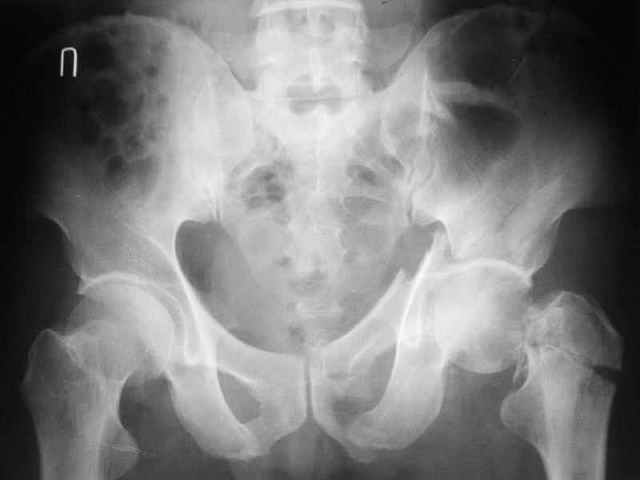

Больной 18 мая 2003 года в автоаварии получил перелом левой вертлужной впадины, вывих бедра. Госпитализирован в один из стационаров области.Вывих вправлен. В последствии бедро вывихивалось еще дважды. На консультацию был представлен снимок от 19.05.03г., больной переведен к нам 3.06.03г. Снимок при поступлении - перелом впадины, задне-верхний вывих бедра. 05.06.2003 г. выполнено открытое вправление вывиха левого бедра и остеосинтез стенки вертлужной впадины двумя винтами. Послеоперационный период без осложнений. Объем движений в левом тазобедренном суставе восстановился полностью. Выписан на амбулаторное лечение в удовлетворительном состоянии с рекомендациями 3 месяца ходить на костылях без нагрузки на оперированную конечность. На контрольных рентгенограммах левого тазобедренного сустава 13.10.2003 г. - признаки консолидации перелома; плотность, форма головки и состояние суставных поверхностей удовлетворительные. Разрешена дозированная осевая нагрузка, на конечность с использованием дополнительной опоры. 19.12.2003 г. больной обратился с жалобами на боли в левом тазобедренном суставе. На рентгенограммах левого тазобедренного сустава 19.12.2003 г., 20.02.04г. - асептичекий некроз головки бедра. 5.04.04г. - эндопротез. Сейчас ходит без трости, не хромает. Особенность эндопротезирования - при удалении винтов прослежена линия перелома заднего края впадины и предложено установить чашку несколько меньшего диаметра, чтобы она была покрыта несломанной частью.

Случай, представленный Вами, совсем не идентичен обсуждаемому. У Вашего пациента был поперечный перелом с переломом заднего края, а в обсуждаемом случае - высокий двухколонный перелом вертлужной впадины.

То есть в представленном Вами случае был перелом заднего типа, в нашем случае центрального. У Вашего больного был застарелый задний вывих, у нашего - перелом шейки. Столь раннее разрушение головки, вероятно, было во многом обусловлено тем, что не была достигнута анатомическая репозиция, головка бедра осталась смещенной кзади, что является частой ошибкой при крупных фрагментах свода.

Необходимость фиксации вертлужной впадины в нашем случае вообще под вопросом, так как конгруэнтность сохранена (вторичная конгруэнтность типична для двухколонных переломов).